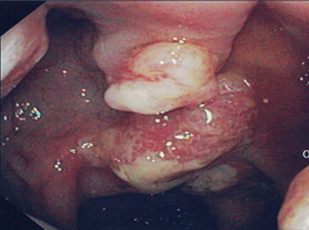

The findings from the boy’s visit 2 years ago were reviewed. On colonoscopy, a thickened appearance of the mucosa of the anterior rectal wall was noted. Rectal biopsies showed mild glandular and smooth muscle hyperplasia, consistent with prolapse change (Figure 2). Biopsies from the other areas of the colon and the ileum were normal.

Figure 2. Photomicrographs of rectal biopsy showing shows colonic type mucosa with mild glandular and smooth muscle hyperplasia, consistent with prolapse change. There is no dysplasia or inflammation.